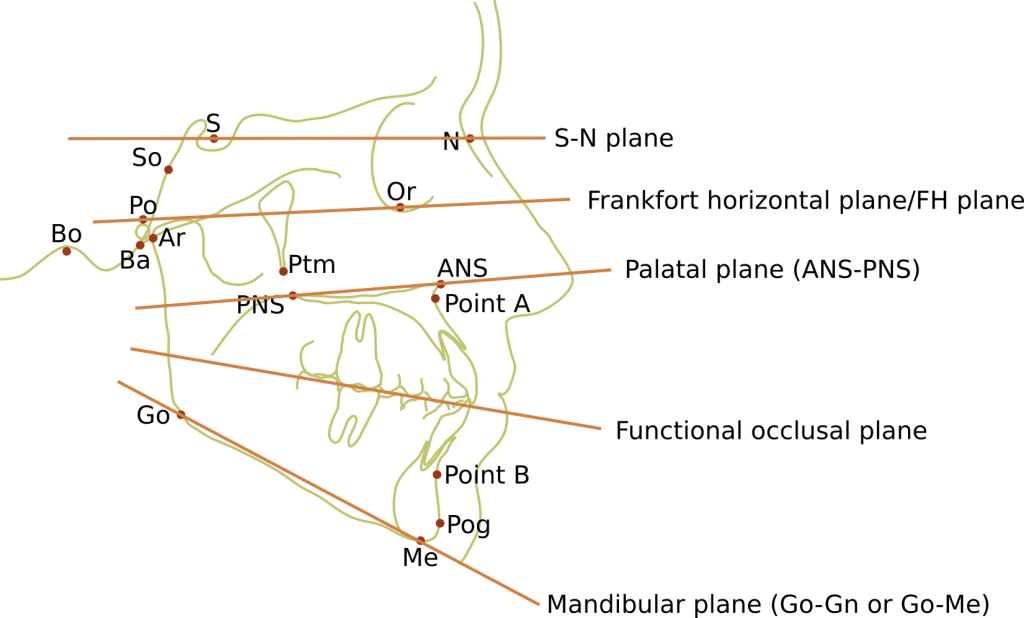

Landmarks for Cephalometric tracing

- Ba – Basion: The most forward and highest point of the anterior margin of foramen magnum.

- Bo – Bolton: The highest point in the concavity behind the occipital condyle.

- Ar – Articulare: The point of intersection of the contour of the posterior cranial base and the posterior contour of the condylar process.

- S – Sella: The midpoint of sella turcica.

- Po – Porion: Outer superior margin of the external auditory canal.

- SO– Spheno-occipital synchondrosis: Junction between the occipital and basisphenoid bones.

- Ptm – Pterygomaxillary fissure: Point at base of fissure where anterior and posterior walls meet.

- Or – Orbitale: Lowest point on the inferior margin of the orbit.

- ANS – Anterior nasal spine: Tip of anterior nasal spine.

- PNS – Posterior nasal spine: The tip of the posterior spine of the palatine bone.

- Point A – Subspinale: Innermost point on contour of the premaxilla between the anterior nasal spine and the incisor tooth.

- Point B – Supramentale: Innermost point on contour of the mandible between incisor tooth and the bony chin.

- Me – Menton: Most inferior point on the mandibular symphysis, the button of the chin.

- Go – Gonion: Lowest most posterior point on the mandible with the teeth in occlusion.

- Pog – Pogonion: Most anterior point of the contour of chin.

- N – Nasion: anterior point of the junction between the nasal and frontal bones.

Cephalometric plane

These are straight lines between two points. There are few you need to know:

- Palatal plane (ANS-PNS).

- S-N plane – represents the anterior cranial base which is often used as a frame of reference for growth because of the early cessation of growth.

- Frankfort horizontal plane/FH plane (P-Or) – habitual horizontal postural position. Often understood as being parallel to the floor. This is regularly used as a reference.

- Functional occlusal plane (FOP) – formed by drawing a line that touches the posterior premolars and molars.

- Mandibular plane (Go-Gn or Go-Me) – connecting the point gonion to gnathion at the inferior border of the mandible.